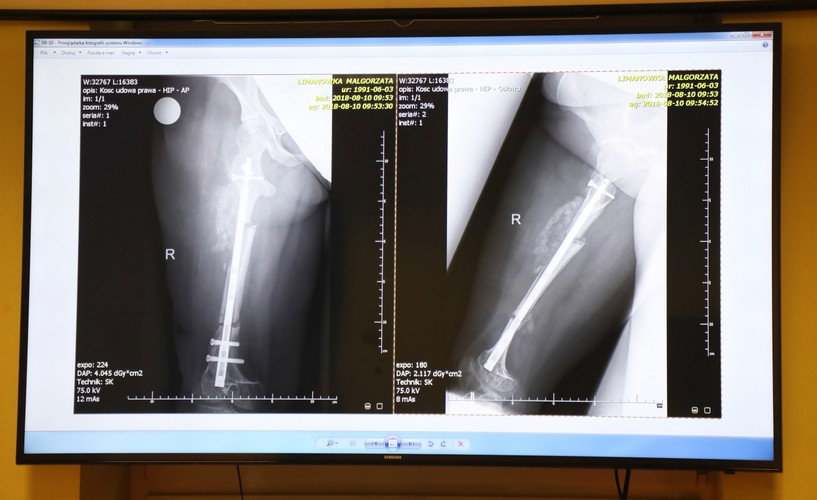

Pierwszą tego typu operację – wydłużenia kości za pomocą pola magnetycznego – przeprowadzono w Szpitalu Specjalistycznym imienia Stefana Żeromskiego w Krakowie. 27-letniej pacjentce cierpiącej na wrodzoną łamliwość kości wszczepiono w kość udową specjalny gwóźdź sprowadzony z USA, przez który przepuszczano pole i stymulowano tym samym kość do wzrostu. Od lipca, kiedy kobieta przeszła operację, do 18 września, kiedy lekarze pochwalili się jej wynikami, udało się wydłużyć kość o 3 centymetry.

3/6INNOWACYJNA OPERACJA WYDŁUŻENIA KOŚCI